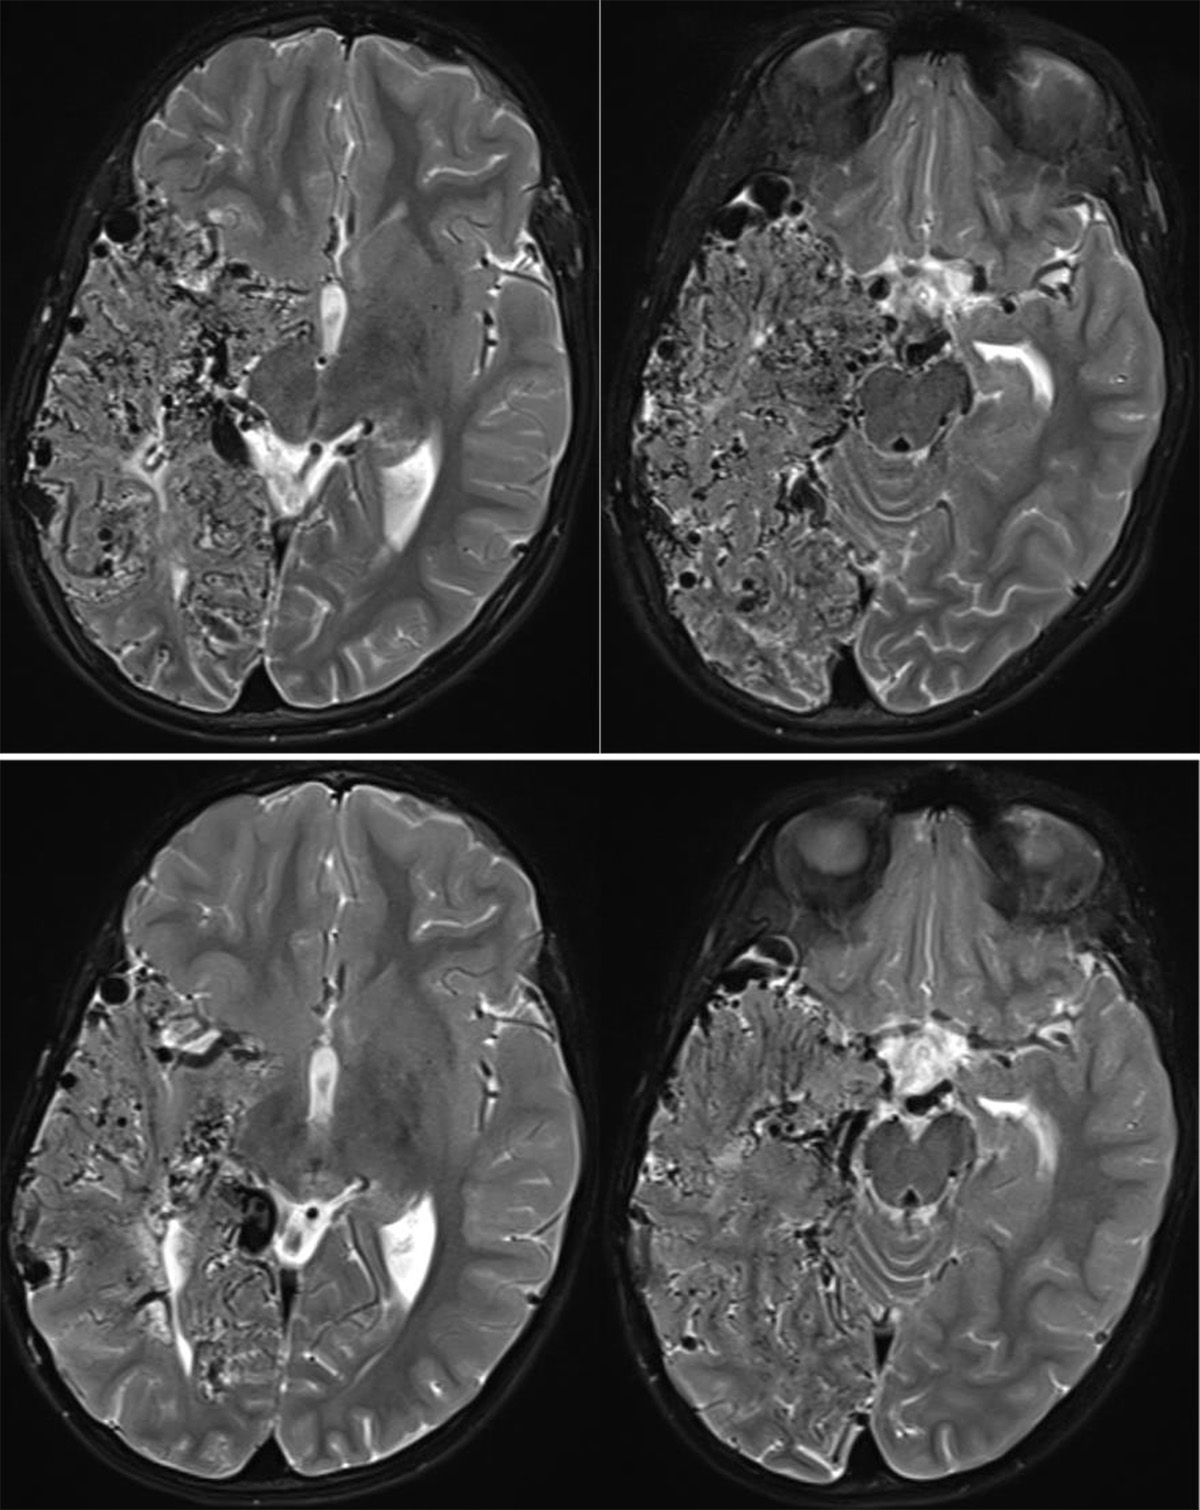

Figure 3

Axial T2WI during second presentation (lower row) and five years later (upper row) demonstrate progression of the vascular network in the right temporal and occipital lobes.